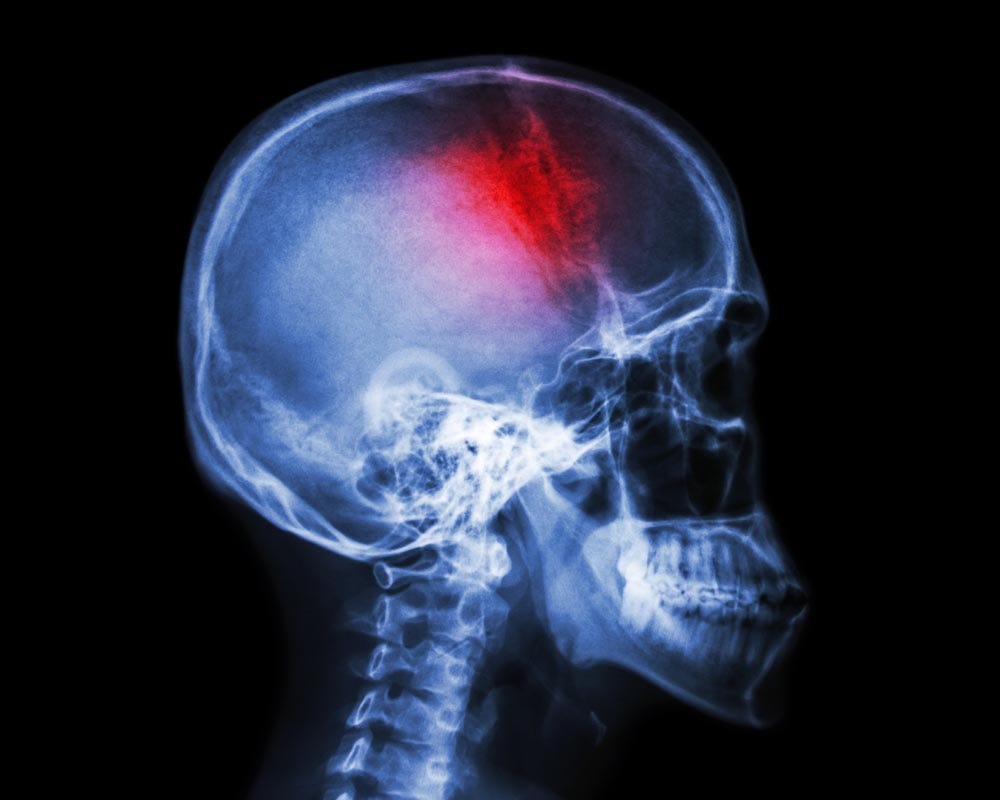

A TIA is described by the Mayo Clinic as a “temporary period of symptoms similar to those of a stroke. A TIA usually lasts only a few minutes and doesn't cause permanent damage.” That’s why it’s sometimes called a “mini-stroke.”

I was kept in the hospital overnight, and went through another battery of tests, this time via machines: an MRI, an x-ray, a CT scan. Every test came back negative, and showed no problems with my brain.

A TIA can be a precursor to a stroke, and about a third of those who have one then have a stroke, and often soon after. Also, I’m not a young man, and have a number of health issues.